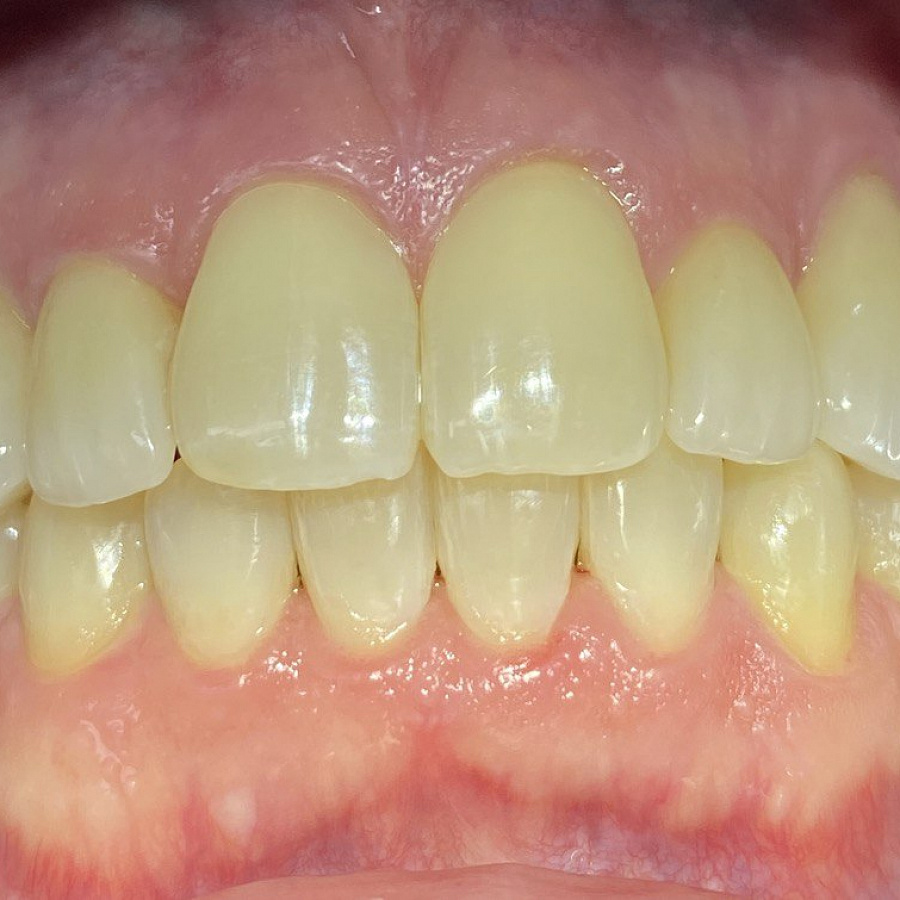

- восстановление плотных межзубных контактов с помощью ортопедических конструкций

- виниры 12, 22 для удлинения резцов.

Ортодонтическое лечение с помощью элайнеров длилось 10 месяцев. Далее последовало протезирование и установка виниров.

Результат лечения